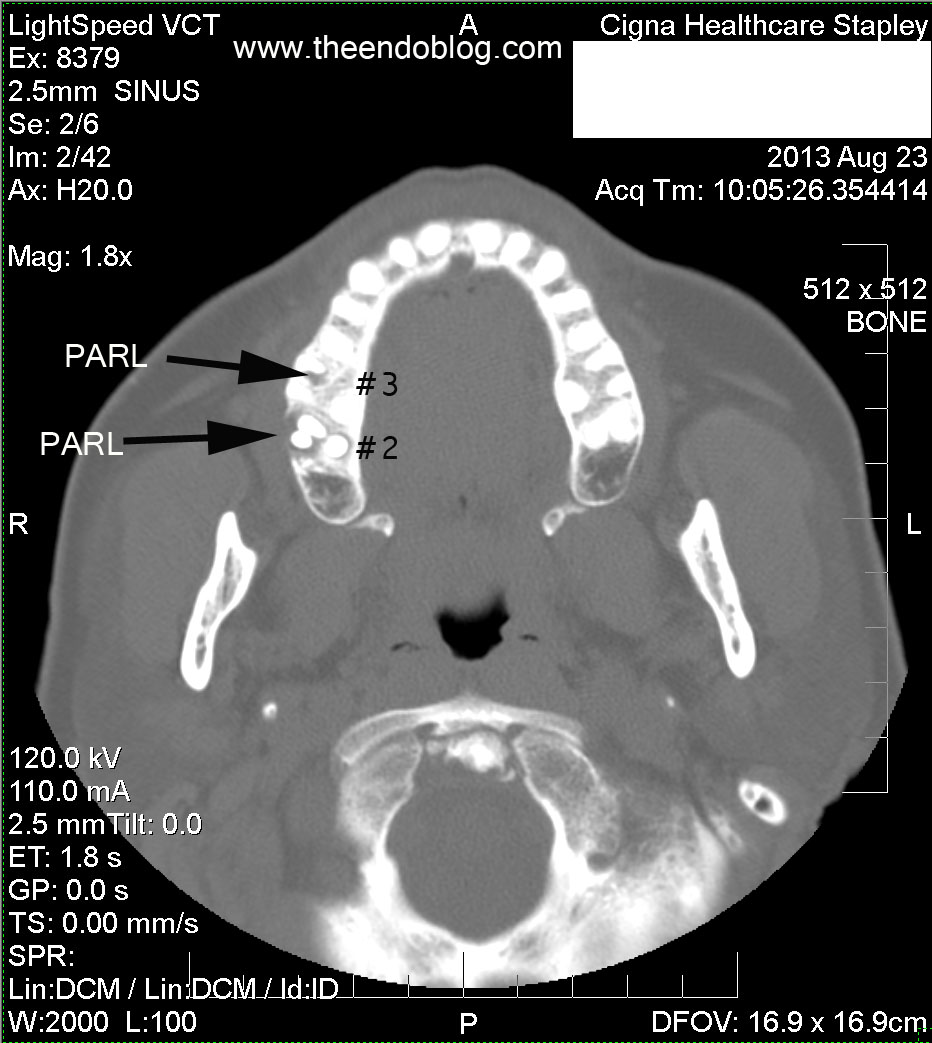

Molar #2 and #3 have periapical radiolucency (PARL), one of which is dehiscent into the maxillary sinus and buccal gingival sulcus.  This may be the most important diagnostic information in the CT scan.  Too often, radiologists and otolaryngologists are not looking at this part of the scan - if it is even included in the field of view.

PeriApical RadioLucency (PARL) seen at apex of MB root - which had a missed canal on initial treatment.